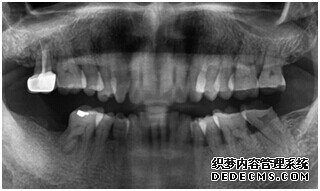

专家诊断:最后一颗牙齿通常不易清洁,且牙齿长了蛀牙之后也不容易发现,很多人就跟 刘女士一样发现的时候就已经是蛀牙中期甚至是后期了,这个时候一定要尽早治疗。不然和刘女士一样必须拔牙是非常可惜的。

由CT片检查来看,刘女士口腔健康环境还是很好的,牙槽骨也适合种植牙的条件,而且由我们最后一颗牙是非常重要的,经过专家的建议和详细解释了原因之后,刘女士选择了美国百康种植牙。